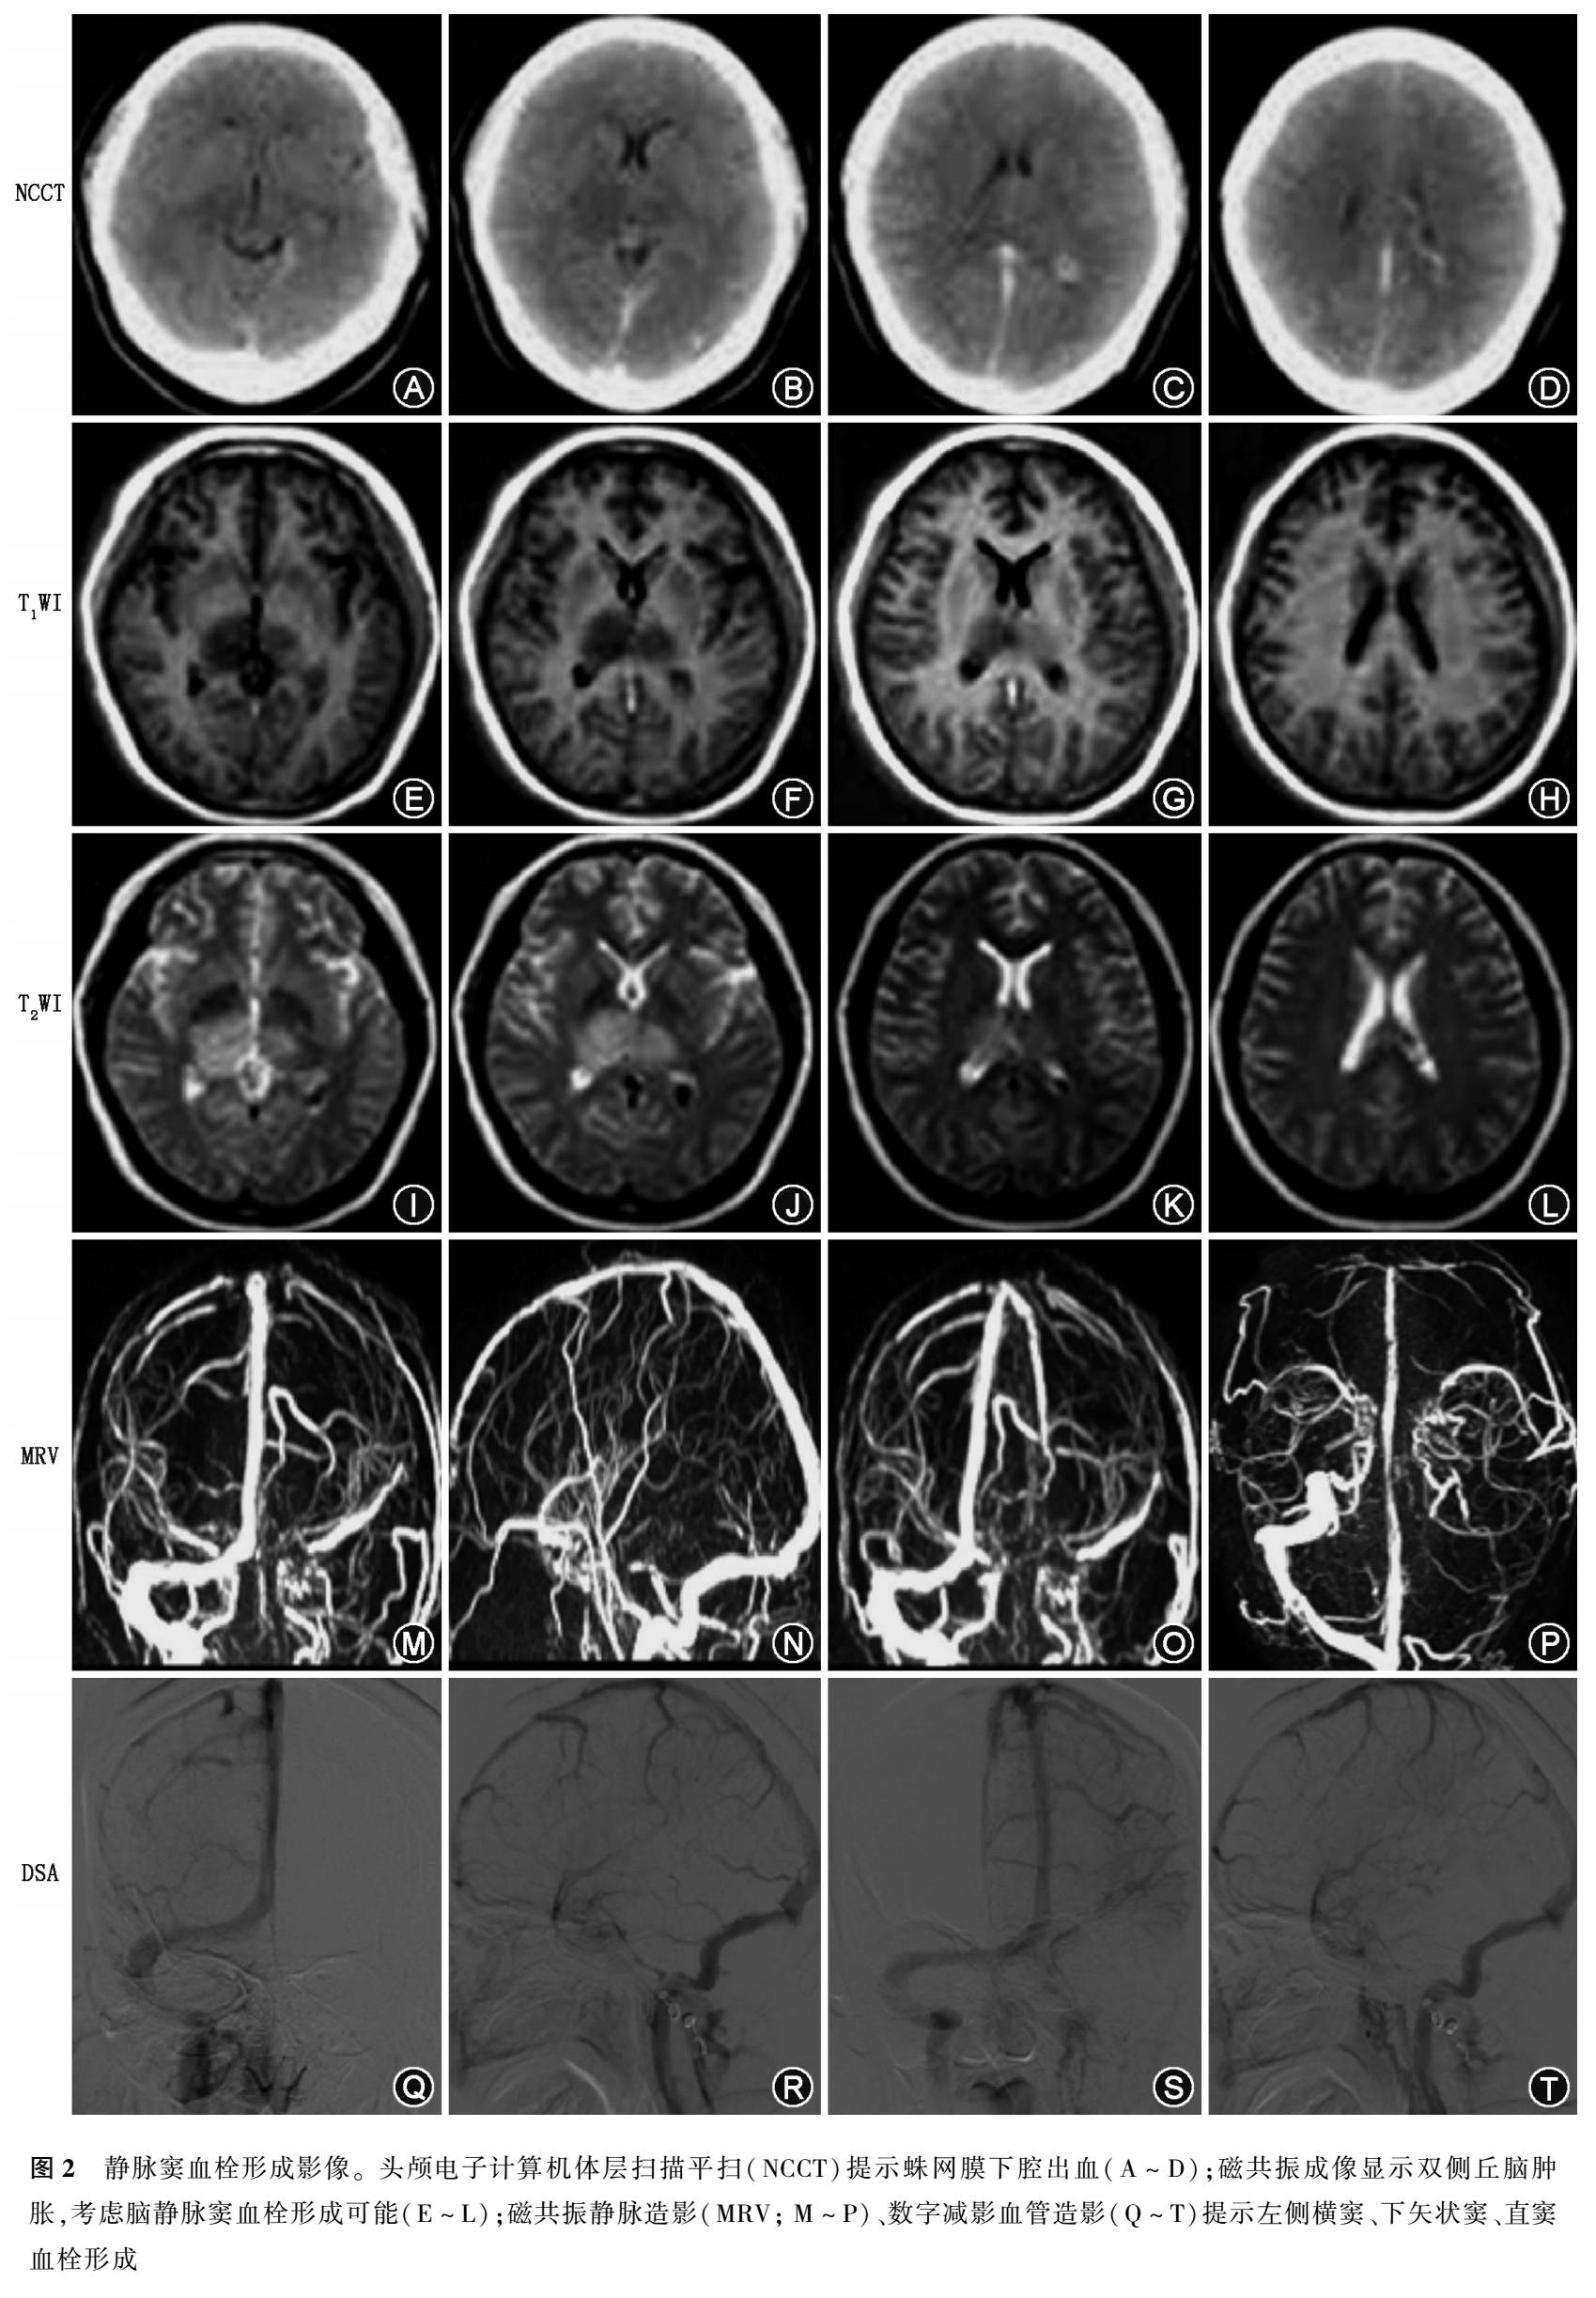

CVST在CT上可分为直接征象和间接征象,直接征象是指血栓本身征象,即静脉窦内三角形或条样高密度(图2A-D),约20%-25%患者可出现,1-2周内消失。但这一征象的特异度并不高,青年人的高血红蛋白血症、红细胞增多症、脱水等均可出现这一征象;间接征象是指血栓形成后的继发征象,包括脑水肿、脑梗死、脑出血、脑静脉扩张以及大脑镰、小脑幕异常强化等。法国一项多中心研究发现,螺旋NCCT出现的高密度征,当密度>70HU,对静脉窦血栓诊断很有价值,但除外上矢状窦水平位的高密度征。Linn等的研究发现,NCCT上出现的皮质下对称性低密度水肿影或高密度出血影或细静脉征在大脑深静脉血栓形成中的敏感度和特异度分别为100.0%和99.4%(图2E-L),而对于皮质静脉血栓形成的敏感度和特异度仅为64.6%和97.2%。

MRV是静脉血流成像,明显受血流速度和伪影的影响,对血流慢的静脉窦和小静脉显示不准确,其信号的缺失有时并不意味血流停滞或血栓形成。但MRV无辐射和无需注射造影剂,临床应用方便,常规应用于静脉系统疾病的诊断(图2M-P),尤其孕妇、肾功能不全患者。CE-MRV能够弥补信号缺失的缺点,对静脉窦血栓的诊断价值更大。

经动脉顺行性造影,不仅能显示各静脉窦的充盈形态、病变静脉窦闭塞程度,还能通过对比剂测定静脉窦显影时间(图2Q-T),一般超过6s为静脉窦显影延迟。